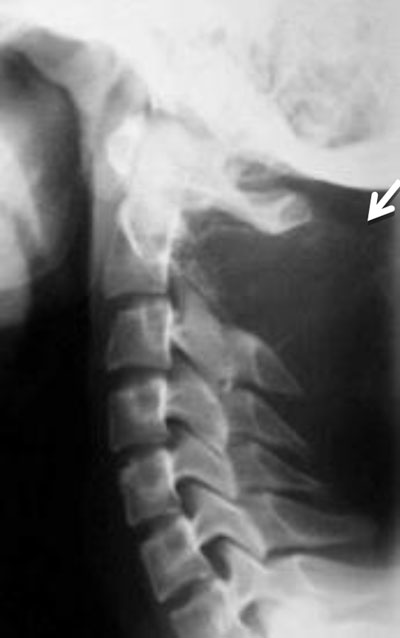

Figure 7

Aneurysmal bone cyst of C2. Lateral radiograph of the cervical spine shows an expansile lesion of the spinous process of C2 (arrow).